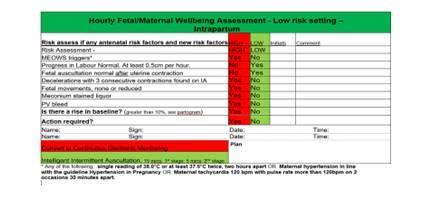

A gentle reminder to support you working in triage:

- Complete the daily checklist for triage to support safe practice, found In a clear folder in triage.

Fetal monitoring practice: Escalate – get support

2. CMiS not reflecting the handwritten notes as shown below: -

When the “onset of labour”, “second stage” or ”pushing commenced” fields are not completed in CMiS, the recorded is rejected by MSDS, as you cannot have a vaginal birth without this information. This means I have to access the handwritten notes to establish the timings and add them to CMiS. I may also send you a friendly reminder.